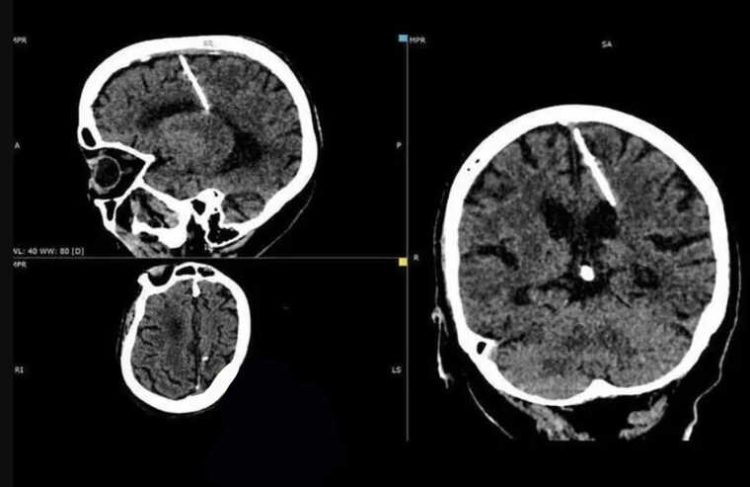

80-Year-Old Woman Discovers That She Has Lived with Metal Needle in Her Brain All Her Life

After undergoing a CT scan, an 80-year-old woman from Russia’s Sakhalin region discovered that she had a 3cm metal needle lodged in the left side of her brain. Photos of the woman’s CT scan results were recently released by the Sakhalin Ministry of Health, along with a shocking explanation. Taking into consideration the woman’s age, […]